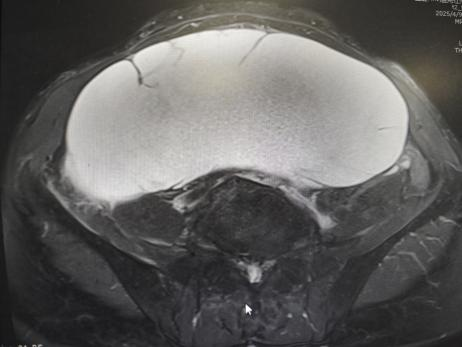

患者67岁,因“排尿不畅”在外院检查发现腹盆腔巨大肿物,转诊至医院后进一步检查,彩超提示:子宫上方可见17.6*19.8*9.3cm囊实性包块,盆腔MRI提示盆腔较大分隔囊性病变,疑似卵巢粘液性囊腺瘤。

患者体形偏瘦,且肿物体积巨大,不除外恶性可能,毗邻膀胱、肠道及重要血管,术中易引发大出血或脏器损伤,且患者年龄较高,麻醉耐受性需精准评估。